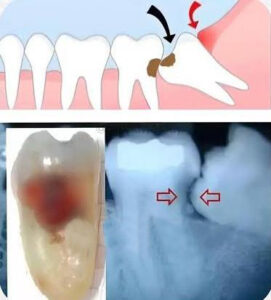

Quando a demora para remover o siso pode causar problemas

Em alguns casos, os dentes do siso não possuem espaço suficiente para nascer corretamente.

Quando ficam inclinados, impactados ou parcialmente erupcionados, ele pode pressionar o dente da frente e provocar: